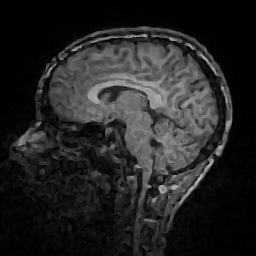

Improving image reconstruction from a sparse set of known pixels was the main motivation behind our work. Therefore, we applied it to two well-known natural images, lena and peppers, as well as to a medical image, a slice of a weighted brain MR scan (t1slice). For lena, we kept a random subset of only of the pixels. Due to the lower resolution of the peppers and t1slice images, we kept and , respectively.

Results for lena are shown in Figure 2, for peppers in Figure 3, and for t1slice in Figure 4. A quantitative evaluation in terms of MSE and AAE is presented in Table 4.1. In terms of the numerical results, our proposed method produced a more accurate reconstruction than any of the competing approaches. Visually, there is a clear difference between second-order (EED) and fourth-order approaches (Li1, Li2, FOEED). Especially, we found that the shapes of edges were reconstructed more accurately. For example, we noticed this around the shoulder and hat in the lena image (Figure 2). Similarly, the white and grey matter boundaries were better separated in the t1slice (Figure 4).